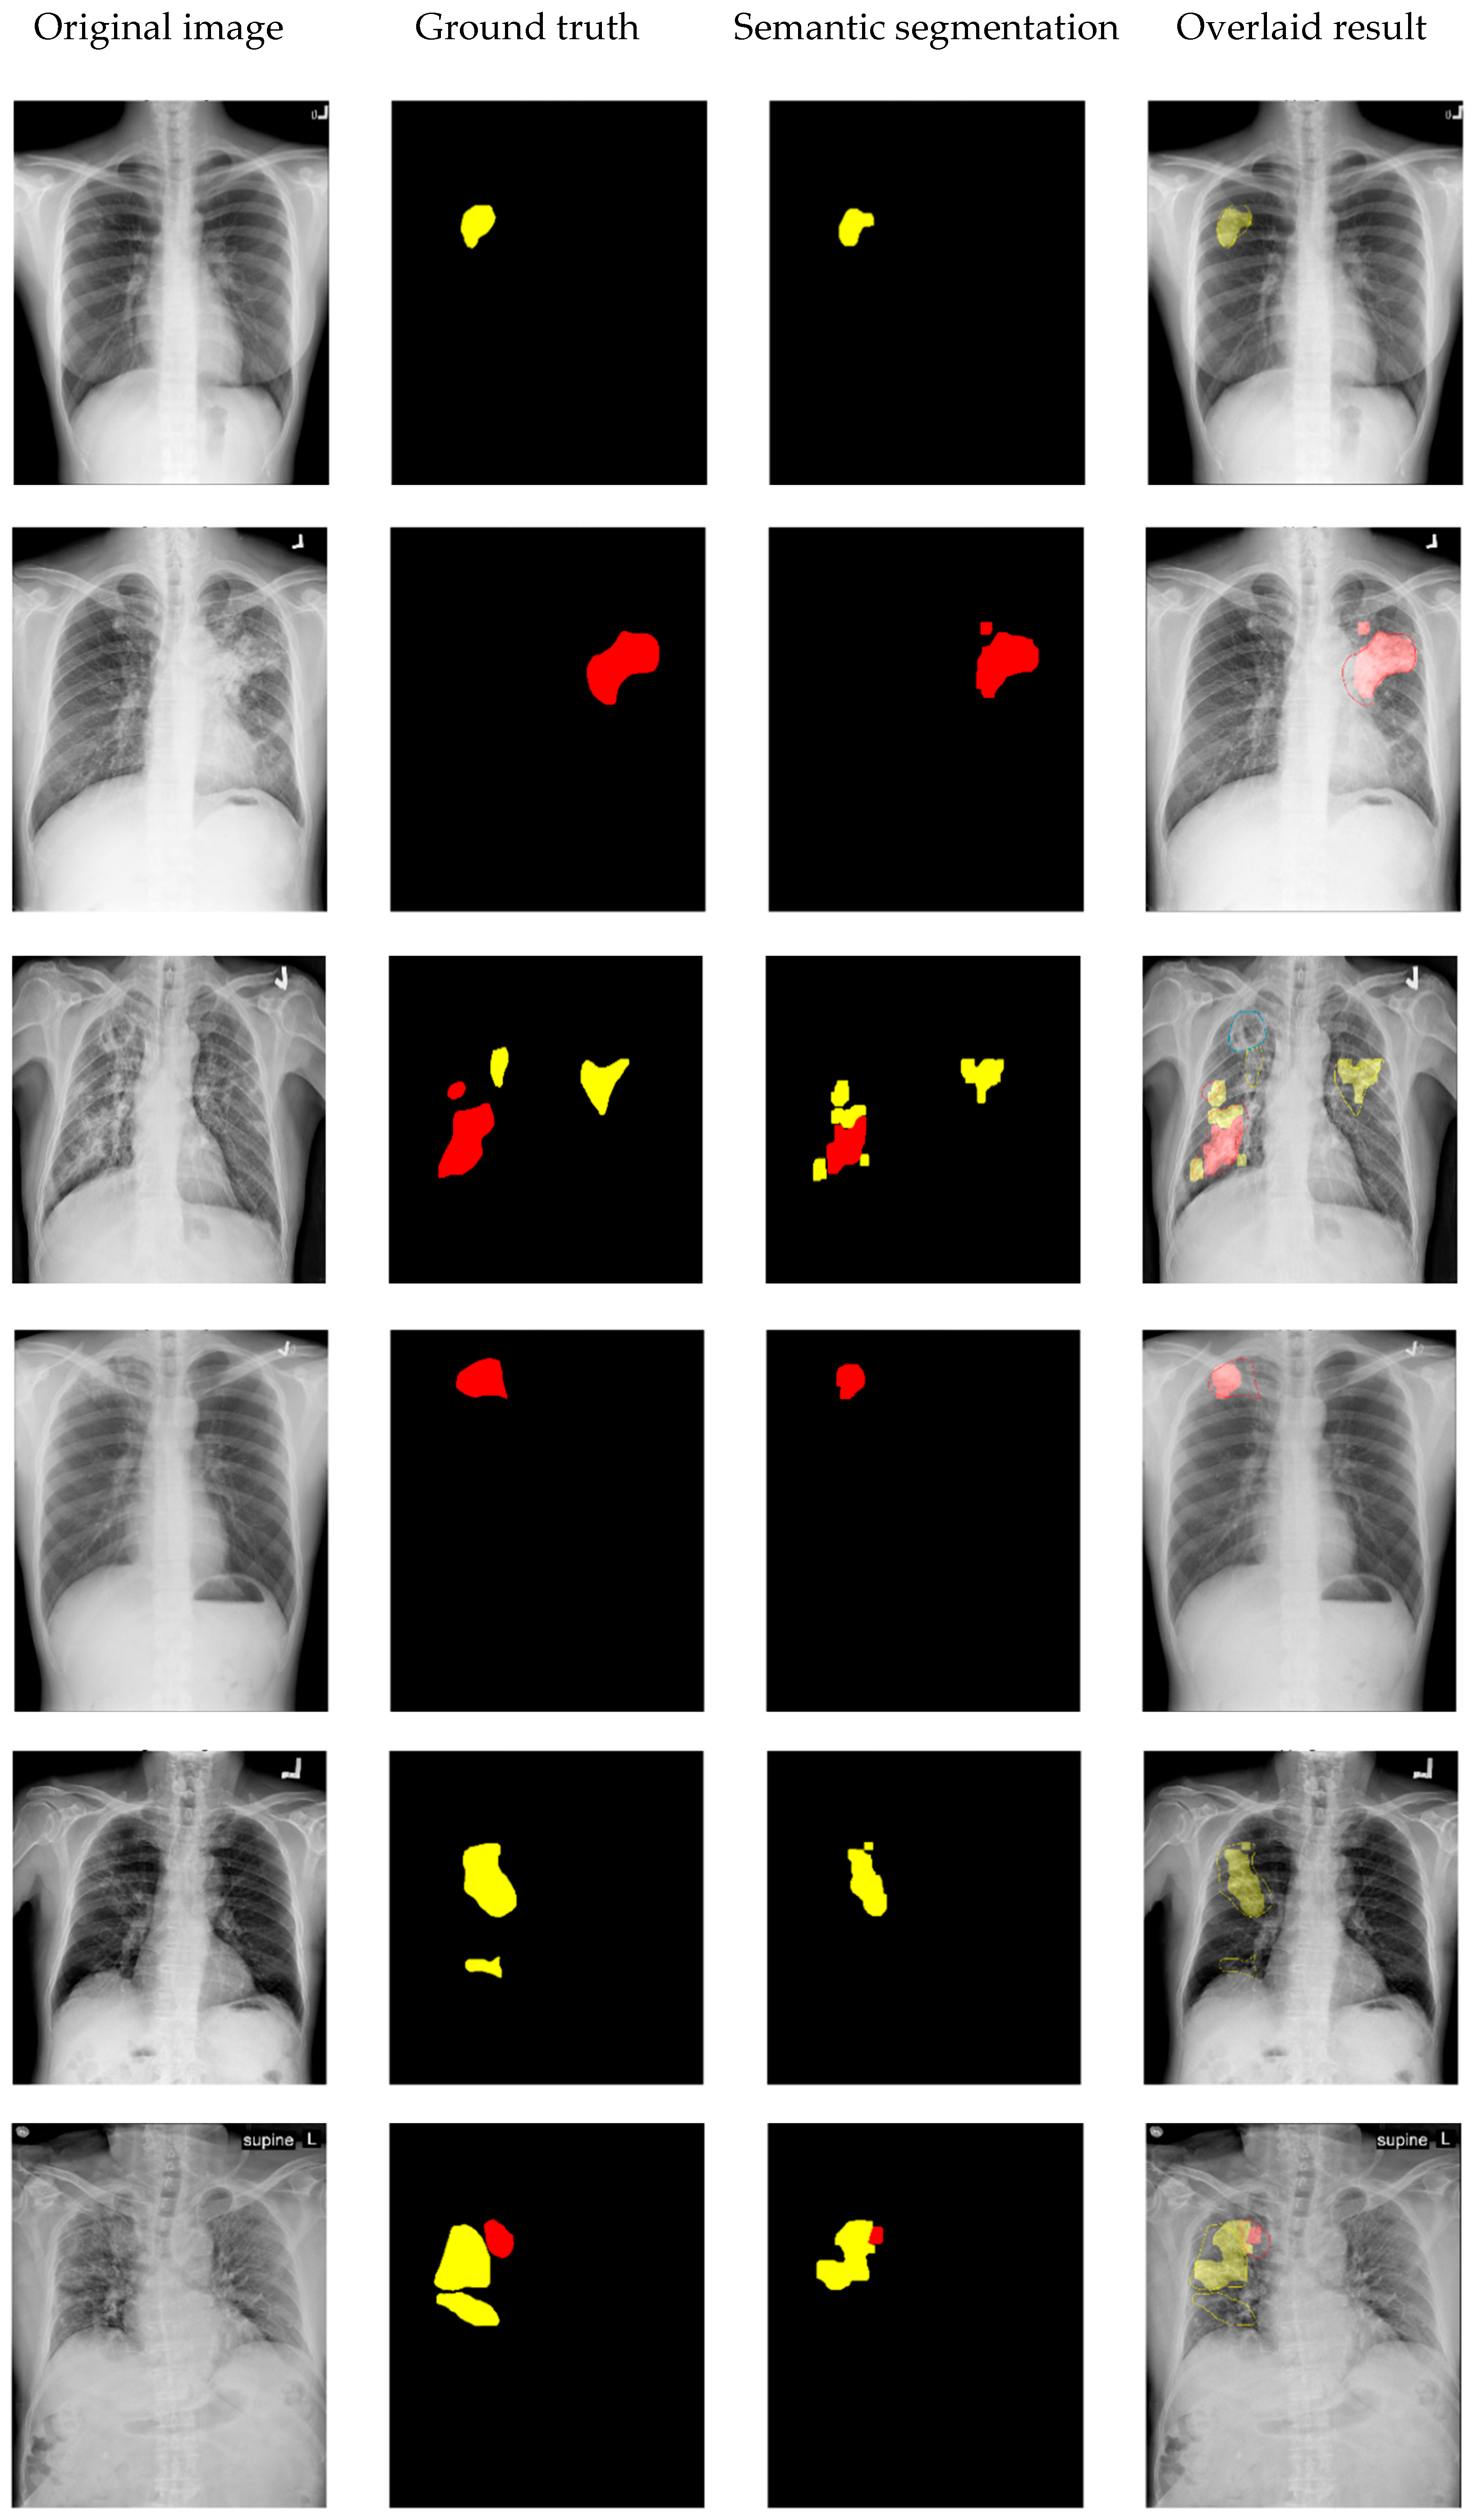

4. Experimental Results and Discussion